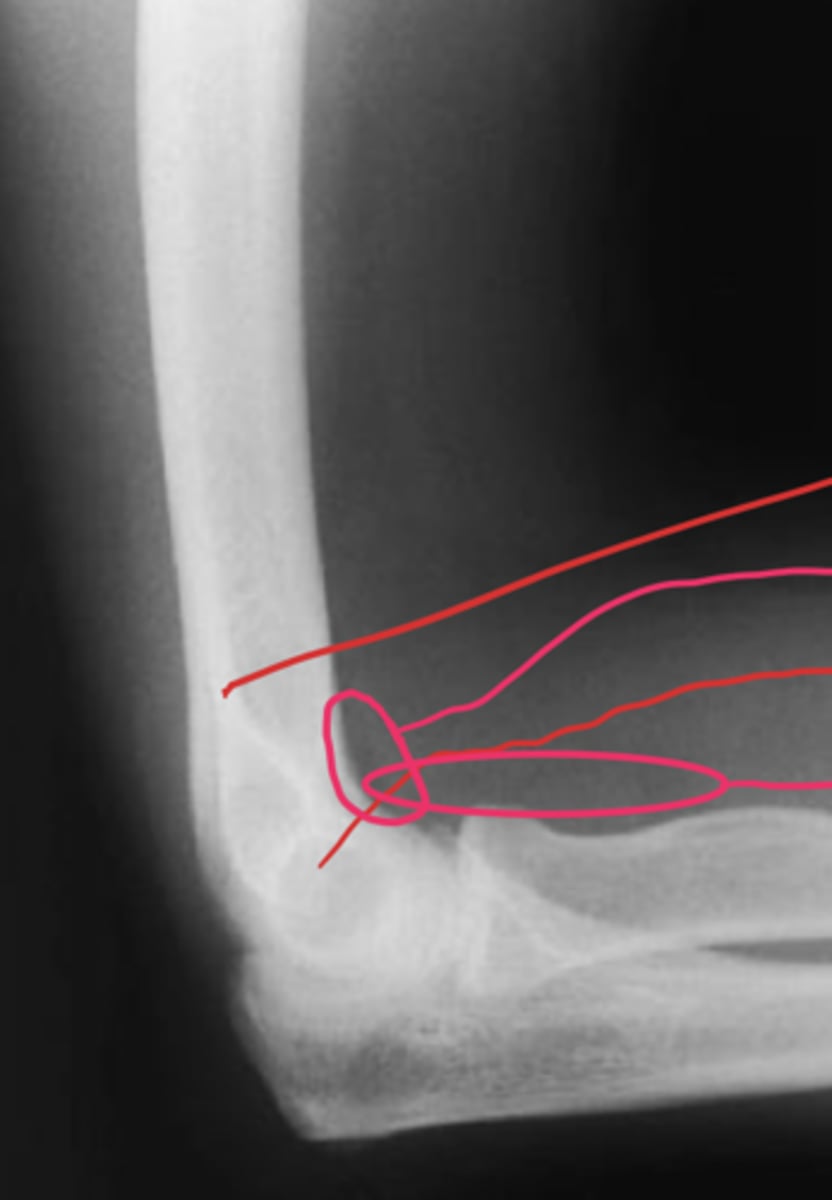

positive fat pad sign

What is the issue?

Lateral elbow

What view is this?